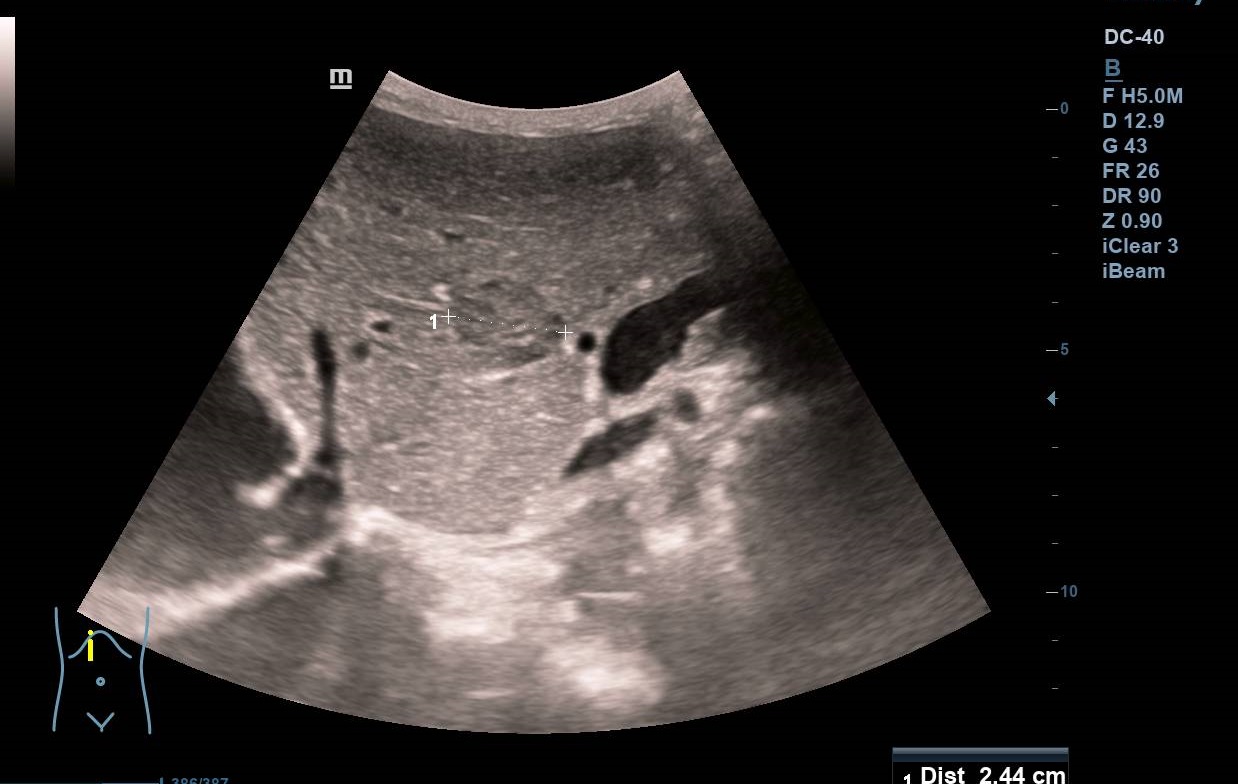

Se observan dos imágenes hipoecogénicas en el parénquima hepático, bien delimitadas, con alguna lobulación a nivel de segmento 3 y en lóbulo caudado de 2,5 y 1,2 cm de diámetro (figuras 1 y 2) y una porta de 13,1 mm de calibre. Se confirman los hallazgos con ecógrafo de consola (figura 3) (vídeos disponibles).

Seis meses después, al revisar la historia su médico advierte que el paciente olvidó su cita y vuelve a derivarlo tras realizar otra ecografía clínica, observando las mismas lesiones sin cambios (figura 4), lo que sugería benignidad. Finalmente se realiza TC: «lesión hipodensa de apariencia sólida en lóbulo caudado de 14 mm y lesión subcapsular de 9 mm en segmento VIII» y RM: «múltiples lesiones hepáticas benignas, la mayoría corresponden a angiomas hepáticos (los de mayor tamaño se localizan en los segmentos 1 y 3), otras se corresponden a pequeños quistes biliares subcentimétricos».